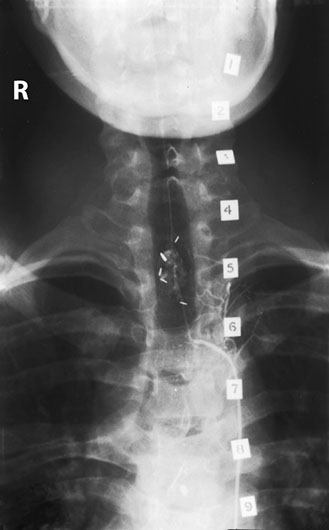

A young man working at the supermarket found his legs becoming weaker and he became unable to push the trolley. A myelogram performed with the help of intrathecal contrast medium demonstrates a tortuous dilated vein flowing along the dorsal aspect of the spinal cord. The conus is dilated, consistent with a syrinx.

A spinal angiogram was carried out. The hairpin bend of the artery of Adamkiewicz was identified in the middle thoracic region and other vessels extending upwards showed a very vascular area at T2. It is important to identify the artery of Adamkiewicz as any fast obstruction of it may lead to infarction in the cord. In many elderly patients the artery is often not found at angiography, presumably due to slow obstruction due to atheroma which can be tolerated.

The small vascular lesion in the lower cervical cord has many small arteries feeding it. and this hyperaemia is responsible for the dilated veins and syrinx.

The patient had a very vascular lesion in the cervicodorsal region consistent with a haemangioma of the cord. The clips are there from past surgical attempts to remove this lesion, but it was impossible to achieve due to rapid bleeding.

In this view we can see the anterior spinal artery flowing beyond the lesion. The patient was hurriedly sent to the operating theater and the haemangioblastoma was successfully removed. The vascularity decreased after embolisation with the patient's own blood clot which inadvertently formed in the catheter.